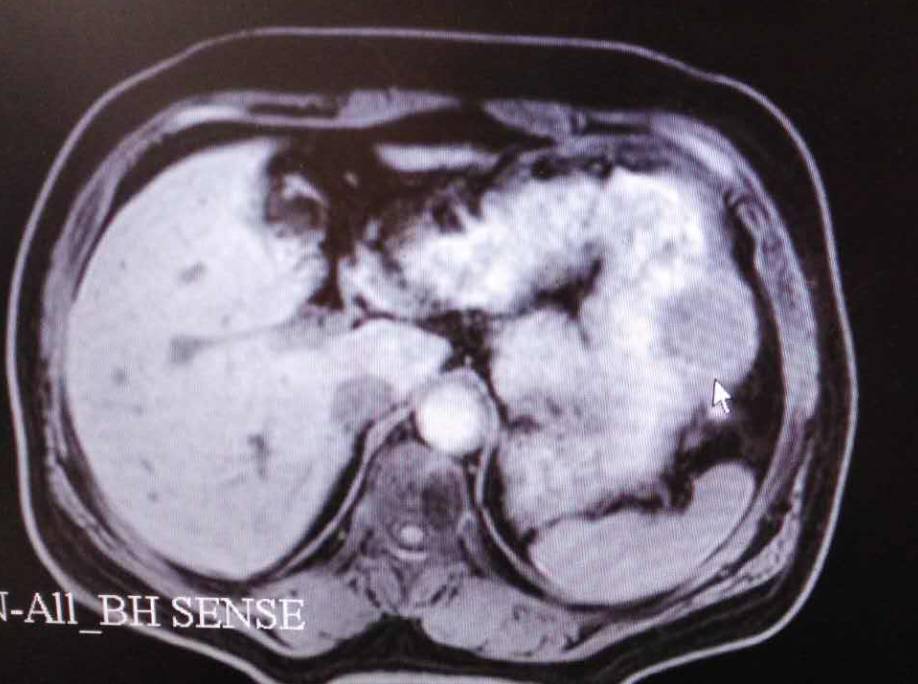

2、一个月前在大连地区检查是胃间质瘤并转移在肝上而后作了手术切除胃三…

真理也是经验:1。这种情况下,手术后最好的治疗就是中医,标本兼治。手术消除了肿瘤,使病人暂时脱离了生命危险。但是手术是治标不治本的,只能切除肿瘤,不能切除肿瘤的病因,比如肝肾阳虚,痰瘀互结。起因是病情在发展,所以我经常看到很多早期癌症患者,术后不做任何治疗,等到复发或者转移的时候才后悔…2.千万不要放化疗。